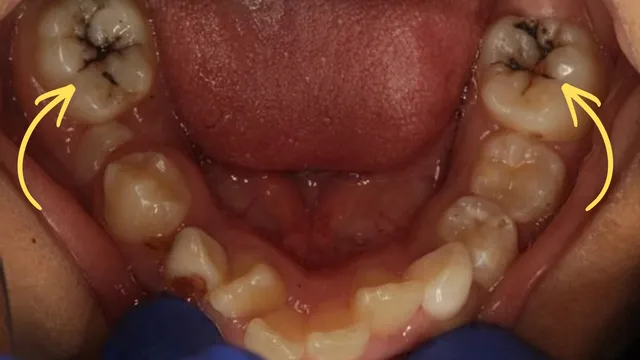

SDF Treatment: Before & After Results

After SDF application, the treated cavity turns black.

This discoloration indicates that the decay has been successfully stopped.

Dr. Abhishek Soni explains this clearly to parents before treatment, ensuring full transparency. In visible areas, SDF may be used temporarily until the child is old enough for a permanent restoration.